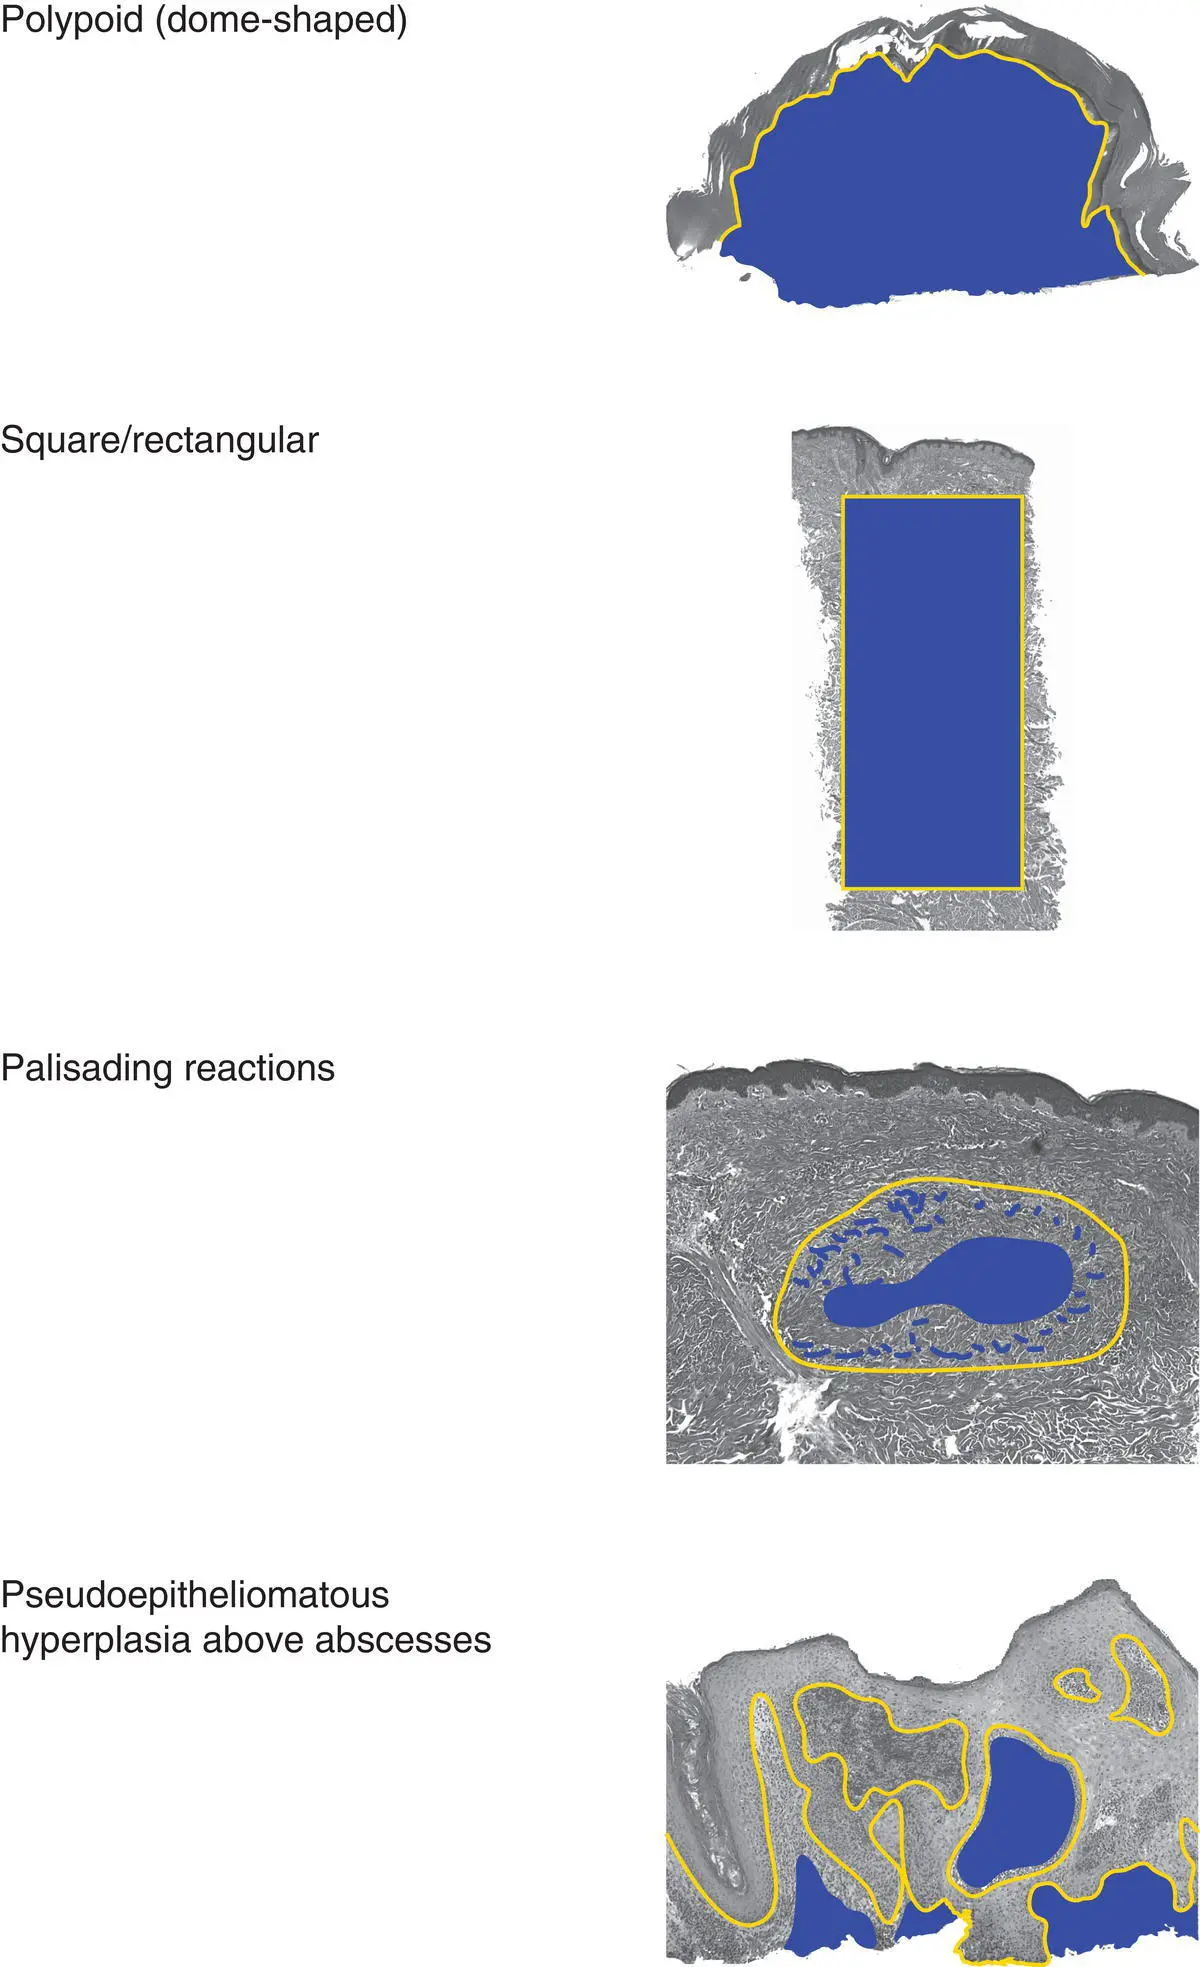

Important characteristics to consider for a tumor/growth include location (A), architecture (B), cell type (C), and benignancy versus malignancy (D). The eye can be trained to focus in on the blue areas (figure–ground separation; grouping)

Figure 2(B)Architecture of an epidermal tumor/process

Dermal tumors can have various architectural patterns